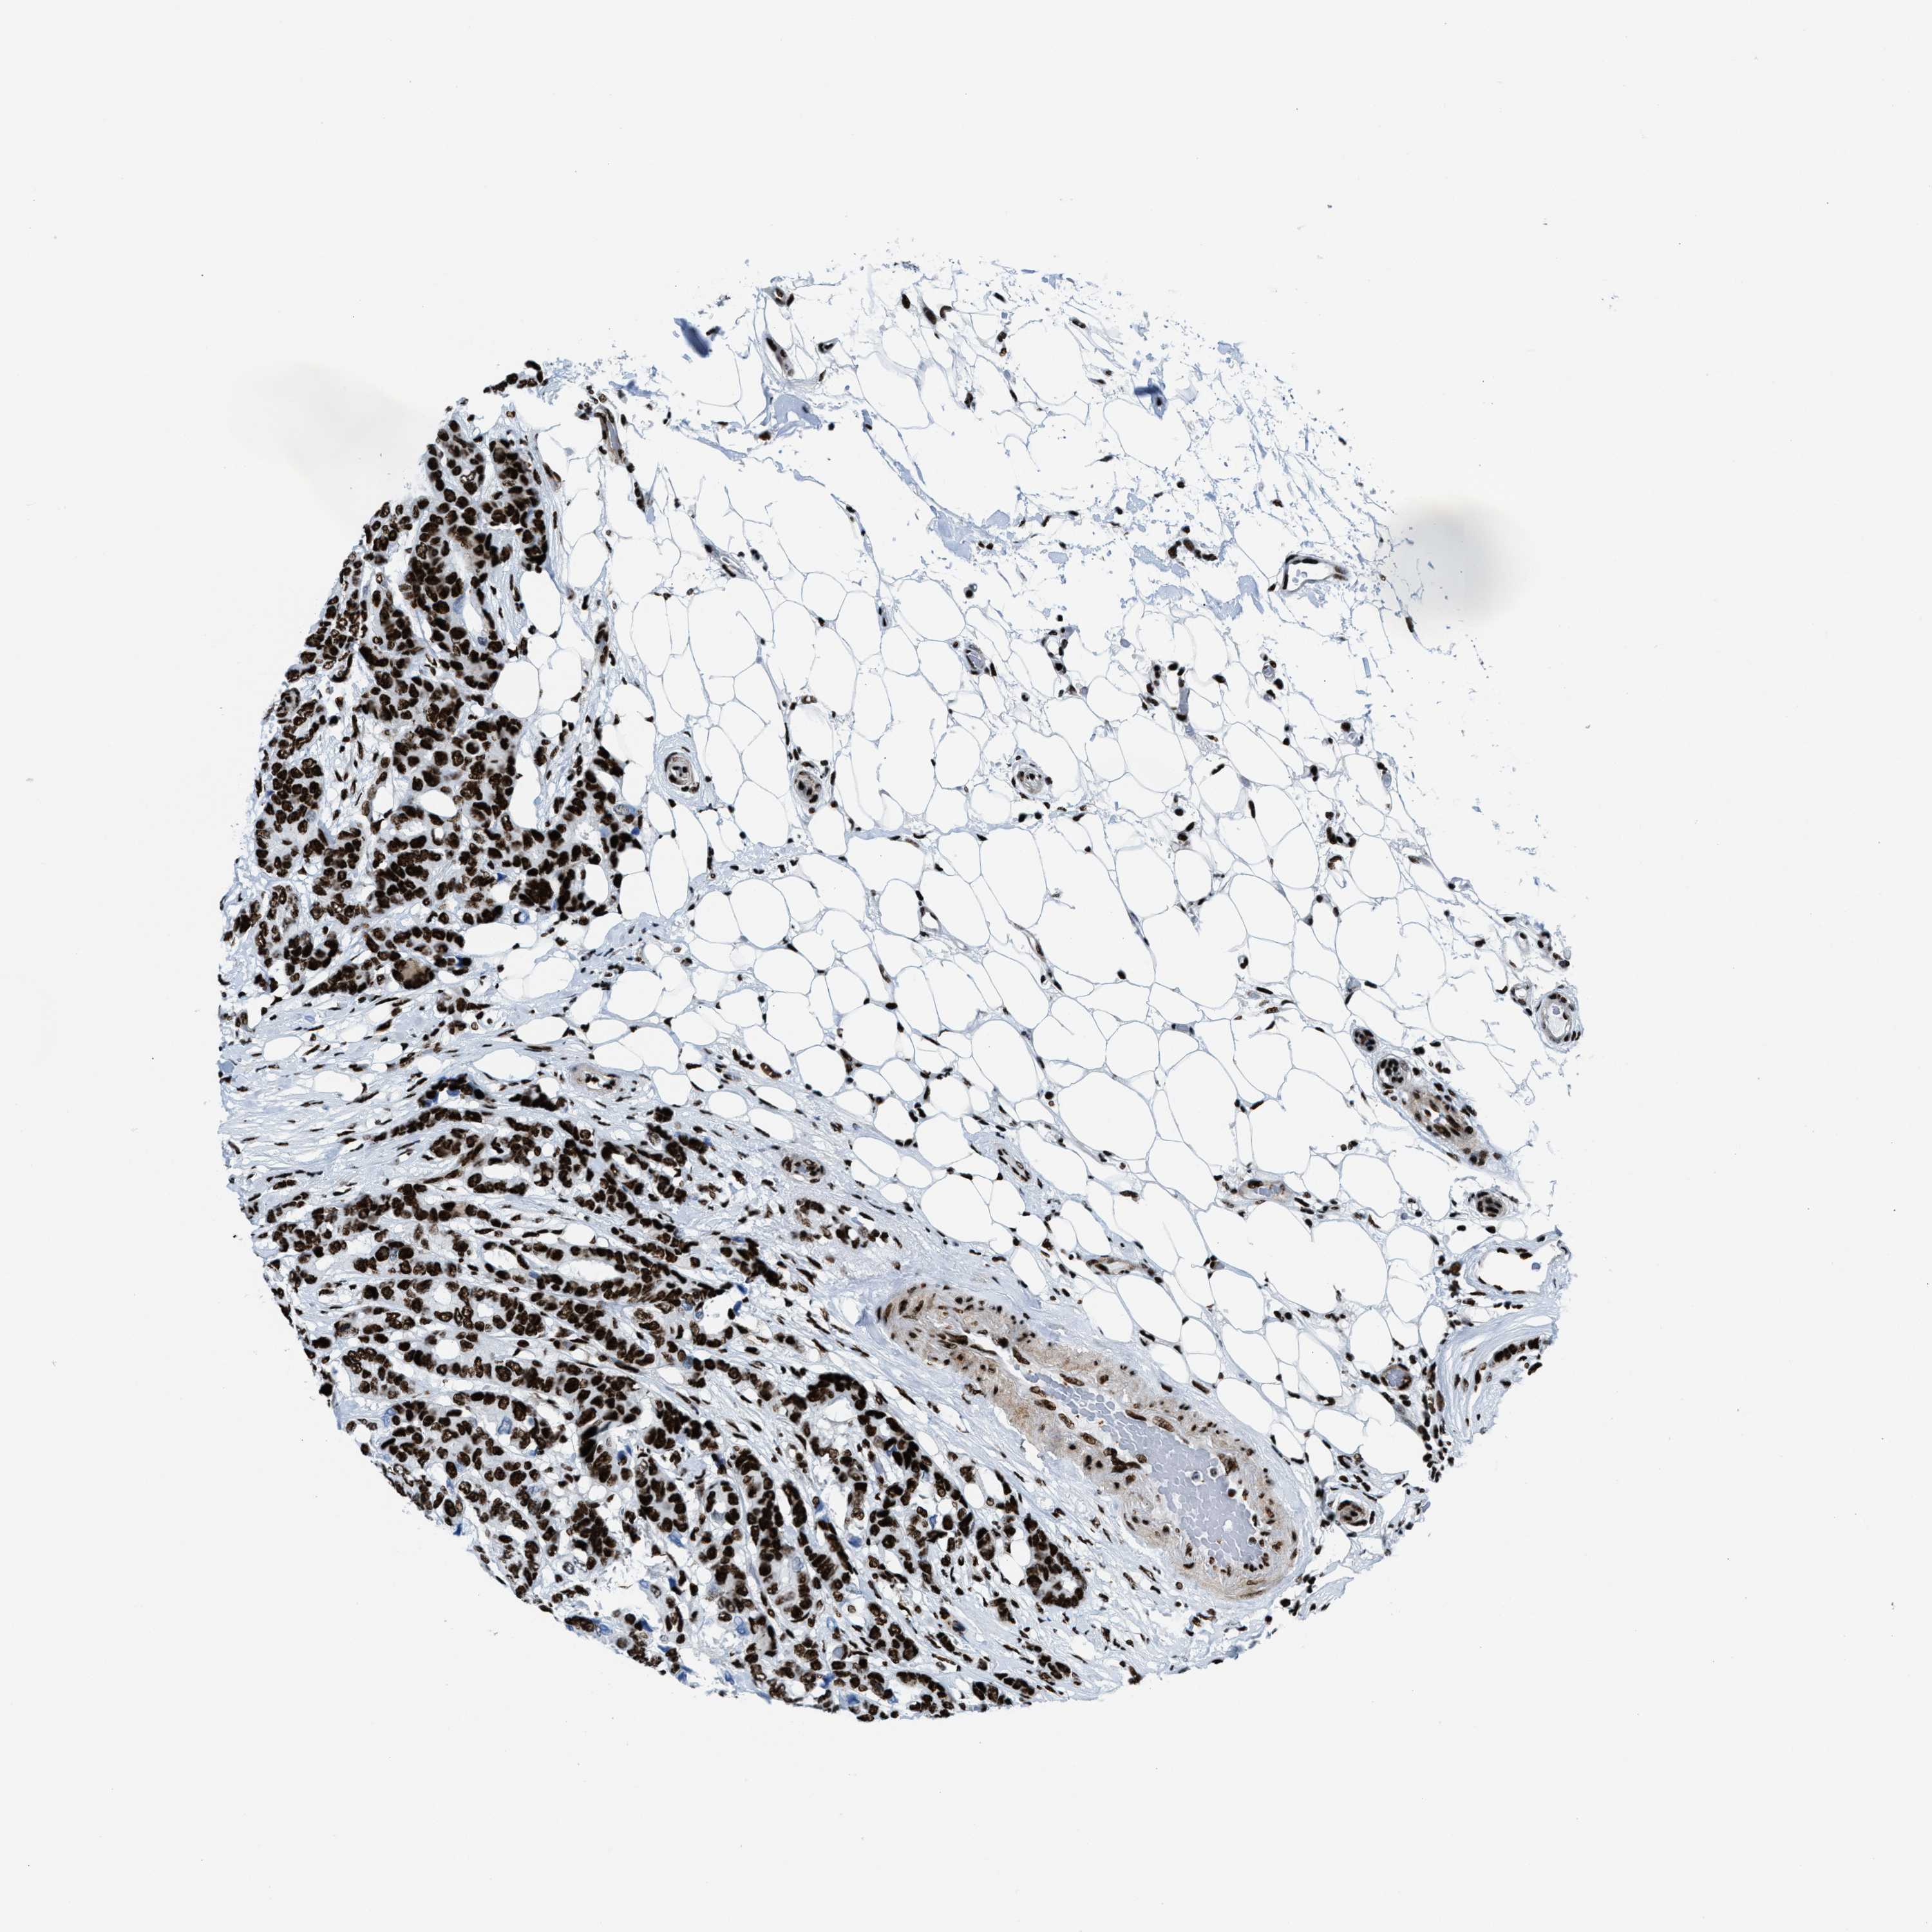

CANCER BREAST CANCER Show tissue menu

BRCA TCGA BRCA VALIDATION PROTEIN EXPRESSION